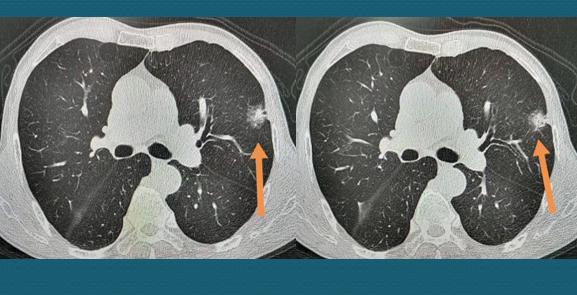

这位老爷子77岁,小便困难半年多,逐渐加重,确诊前列腺肥大准备手术,术前查体发现肺癌:

这个肿瘤表现为实性结节,有分叶和毛刺,并牵拉临近胸膜,具备典型的恶性征象。

老人先做了前列腺手术解决小便问题,又采用胸腔镜微创切除了肺肿瘤,病理是浸润性肺腺癌伴粘液腺癌,未见神经及胸膜转移。

这位老爷子还需要密切观察,防范复发。